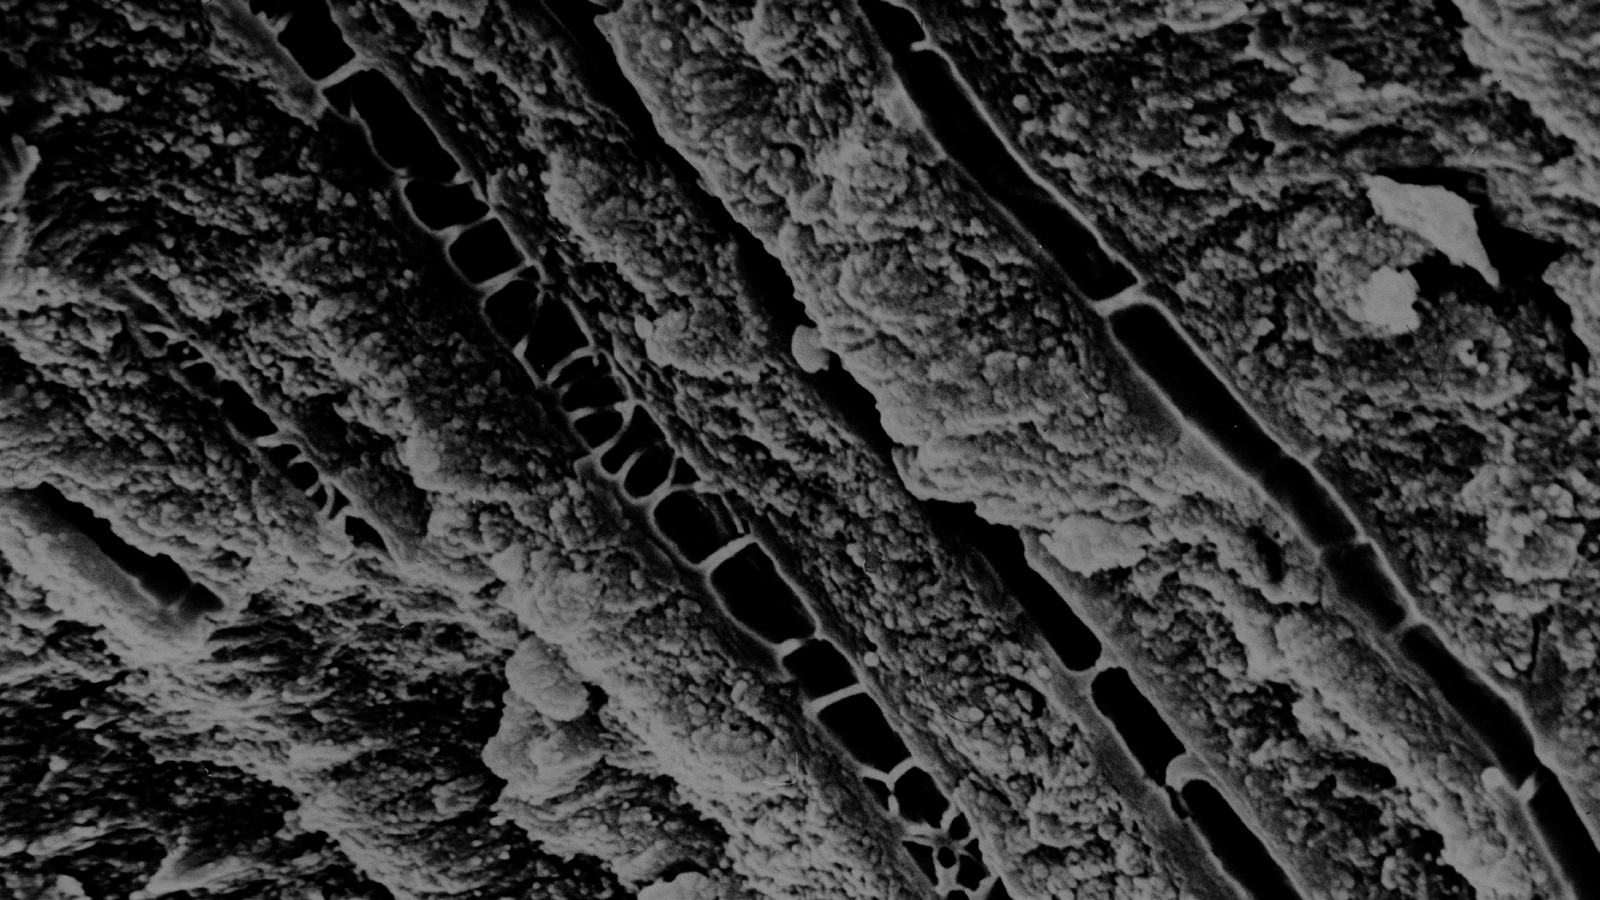

SEM of GLUMA-induced septa in dentinal tubuli.¹

Gluma-induced septum in dentinal tube

SEM magnification of a single Gluma-induced septum in dentinal tube.¹